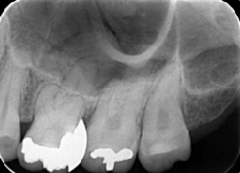

歯周病が進行し、グラグラして物が嚙めず、抜歯してインプラントにしていくことに。

インプラントはストローマンを使用、上部構造はジルコニアセラミックス